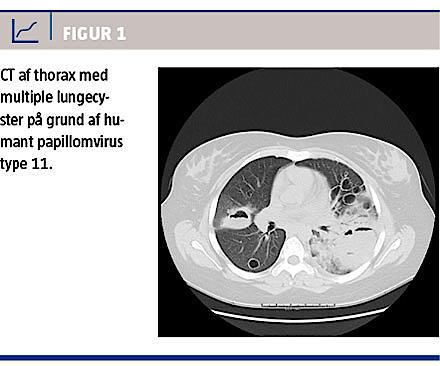

En røntgenoptagelse af thorax viste multiple bilaterale lungecyster, flere med væskespejl, infiltrative forandringer bilateralt og venstresidigt pleuraekssudat. Begyndende cystedannelse blev genfundet ved sammenligning med ét år gamle røntgenbilleder. En supplerende CT (Figur 1) viste multiple tyndvæggede, cystiske forandringer i lungerne, flere med væskespejl, samt afsnitsvis dilaterede bronkier og forstørrede lymfeknuder i mediastinum.

Lungecyster bør haves in mente hos patienter med JLP og symptomer på pneumoni. Diagnosen stilles bedst med CT, og det bør overvejes, om patienter med JLP fremover skal screenes for lungecyster.